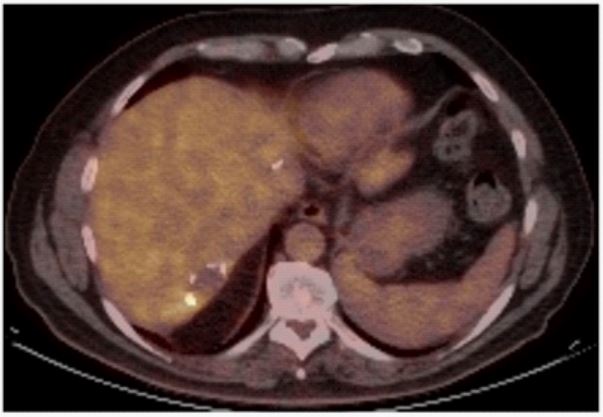

CT-imaging eleven months later detected lymph node disease in the hepatic hilum, while PET confirmed an abnormal metabolism in the hilar lymph node and in the liver parenchymal section of previous segment IV resection (SUV 6,9) (Figure 3). After second line chemotherapy, a new surgical exploration was performed with lymph node clearance. Intraoperative liver ultrasound detected no lesions in the segment IV section and the biopsy performed at this site showed fibroadipose tissue without histological abnormalities., while lymph node disease recurrence was confirmed.

Figure 3: Representative images of PET-CT metabolic activity in the site of previous wedge resection on segment IV (SUV 6,9)